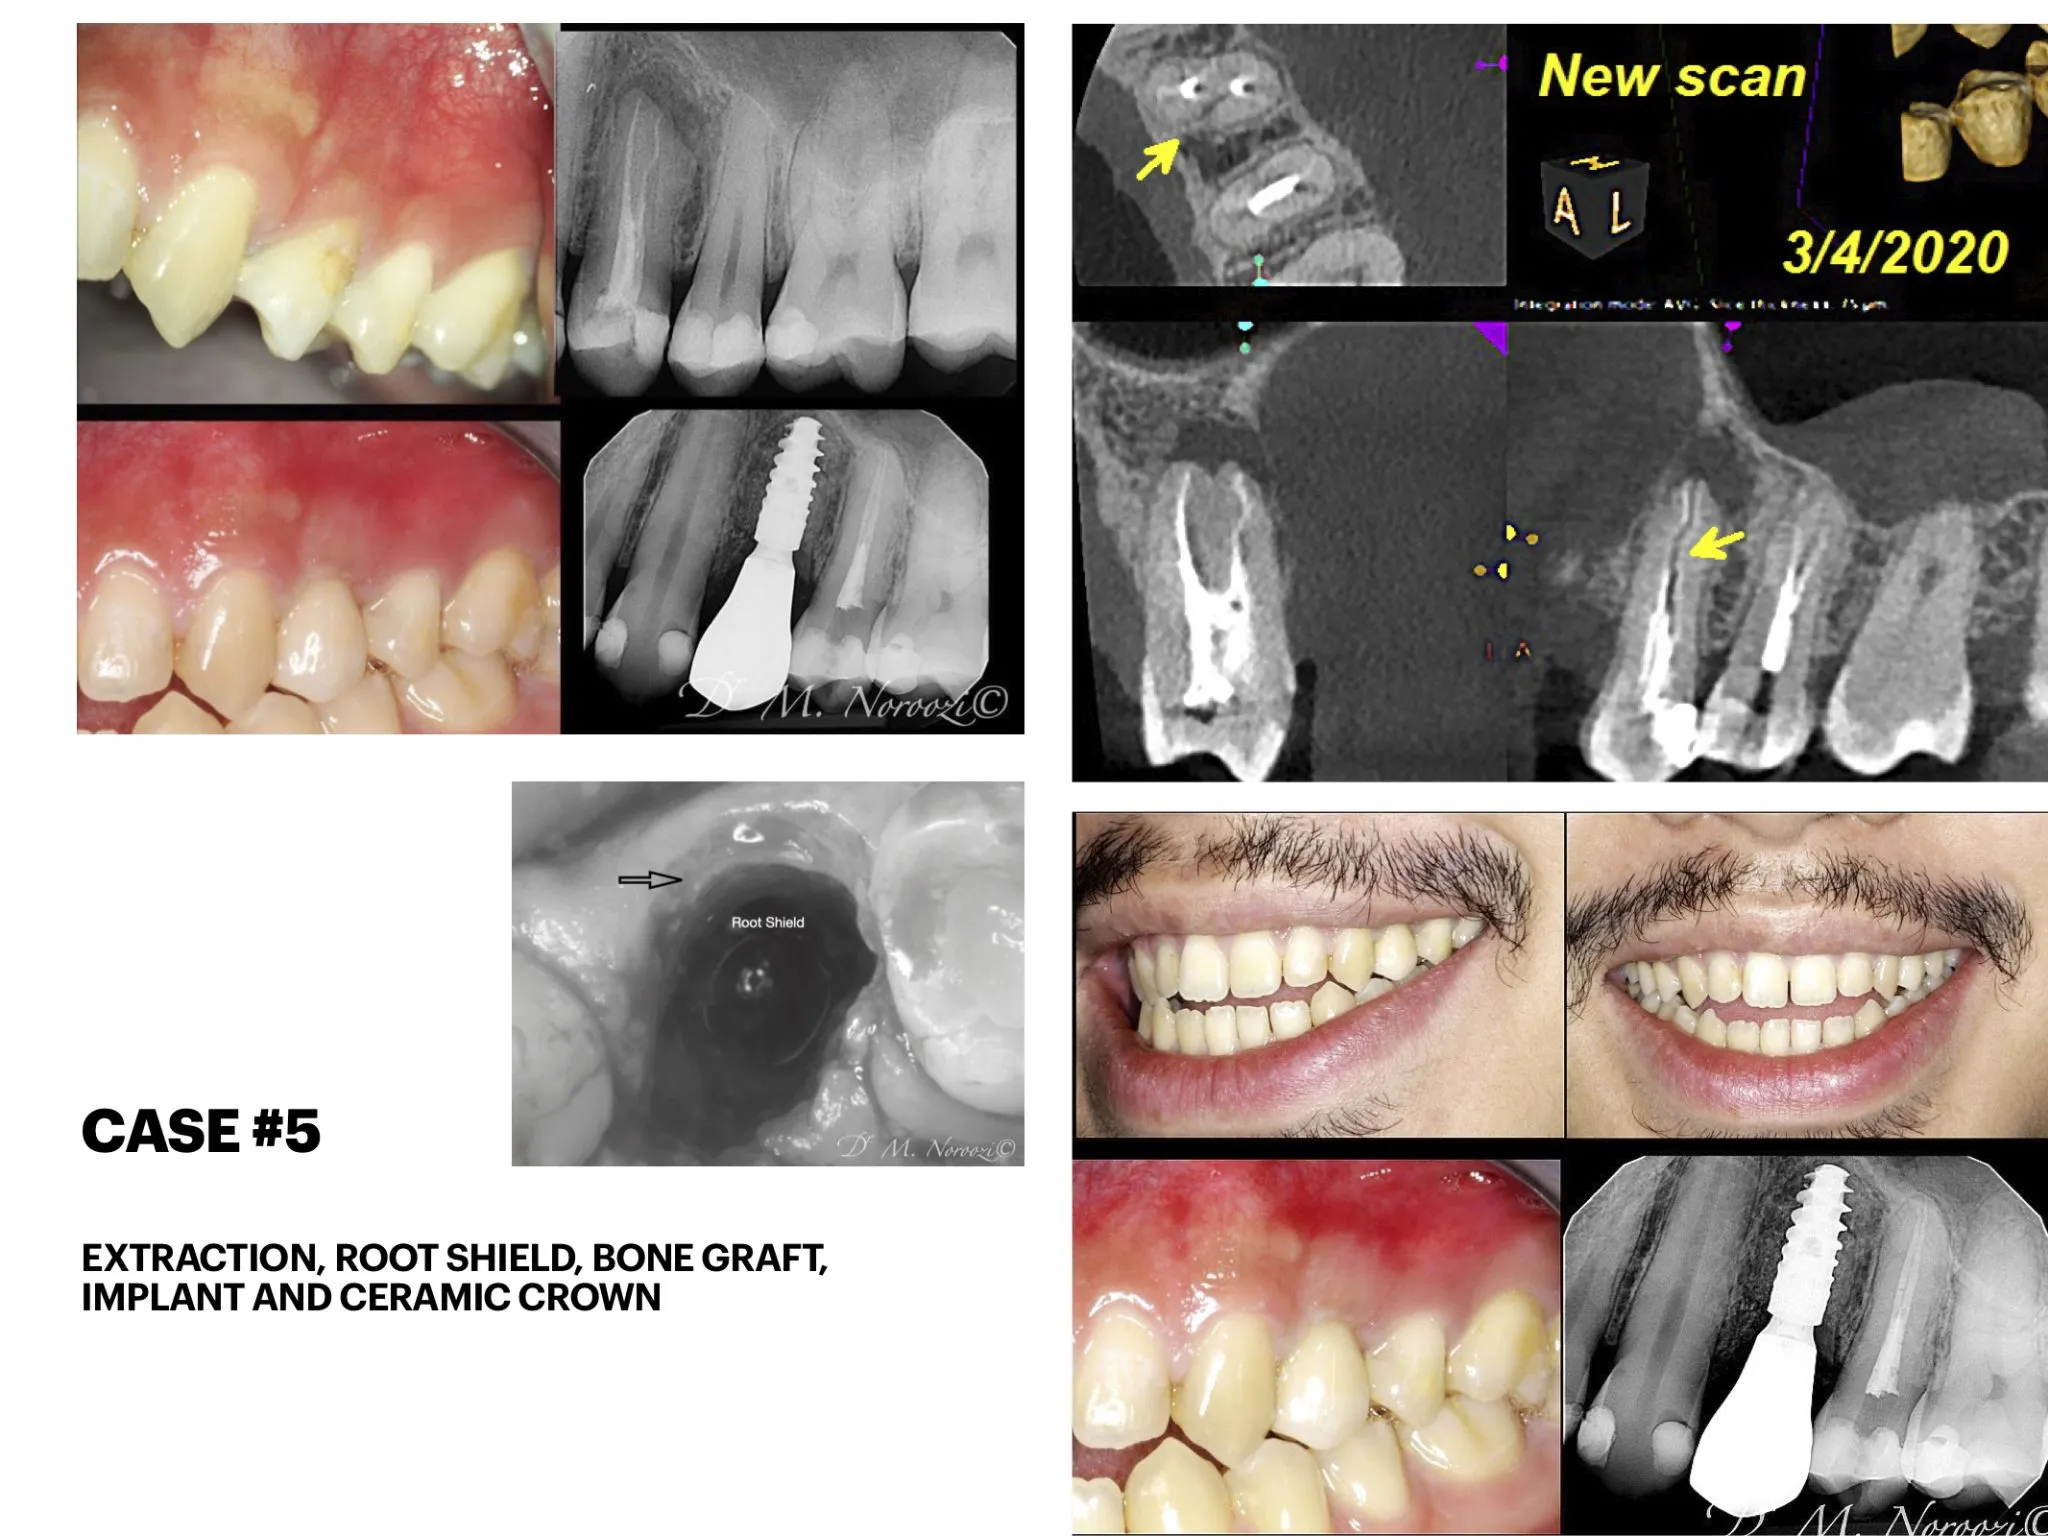

IMPrESS Perio Immediate upper front implants with partial extraction therapy, guided surgery and provisional and final crowns

Front Teeth Dental Implants in Vancouver

IMPrESS Perio Immediate upper front implants with partial extraction therapy, guided surgery and provisional crowns

Front Teeth Dental Implant Bridge by Vancouver Dr. Noroozi Implant Specialist